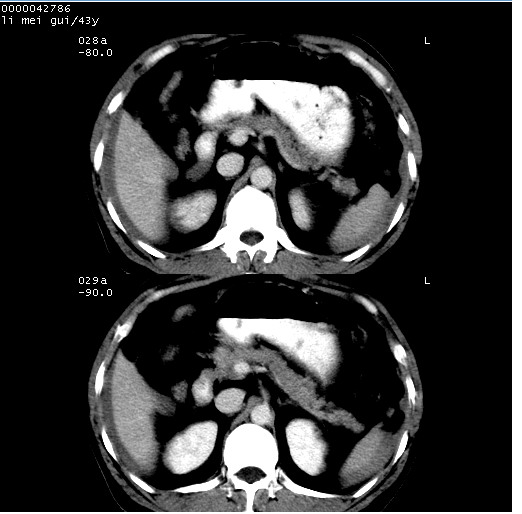

| 患者,男,43岁。突发腹痛2小时,面色苍白,难以平卧。自述近期无明确外伤史,为摩托车驾驶员。 腹部b超检查:脾脏中上极回声异常,肿瘤待排。 临床诊断:腹痛原因待查。 上中腹部ct轴位平扫+增强扫描(层厚10mm,螺距1.0,重建间隔10mm),图像如下: ![]() ![]() ![]() ![]() ![]() ![]() ![]() ![]() ![]() ![]() ![]() ![]() ![]() ![]() ![]() ![]() ![]() ![]() ![]() ![]() ![]() ![]() ![]() ![]() ![]() ![]() ![]() ![]() ![]() ![]() ![]() ![]() ![]() ![]() ![]() zrs发言:支持脾破裂 wwp发言:支持脾破裂并腹水。 xulianj发言:脾脏肿瘤破裂可能性大 zsl6918发言:不像肿瘤出血,考虑还是与外伤后引起的慢性出血有关 zzyy发言:平扫见肝周及脾周积液,脾内密度不均。脾内肿瘤较少见。还是外伤性脾破裂。 沈丘东方医院发言:脾门区一个不均匀强化病灶与其周液体相连多考虑脾占位破裂出血 yixianman001011发言:脾破裂并腹水是可以肯定的,具体原因多以肿瘤性破裂出血,脾脏淋巴瘤可能性大. 结果: 术后,经详细询问患者,其仔细回忆:一月前骑摩托时左侧腰部与别人有“轻微”触碰,因责任在自已,当时又无明显不适,未引起注意。 临床术后诊断:脾破裂并失血性休克(1.外伤性迟发性脾破裂。2.脾脏肿瘤破裂?) 术后标本病检:脾破裂并出血,未见明显肿瘤成份。 原贴地址:http://www.radinet.com.cn/forum_view.asp?forum_id=4&view_id=34070 |